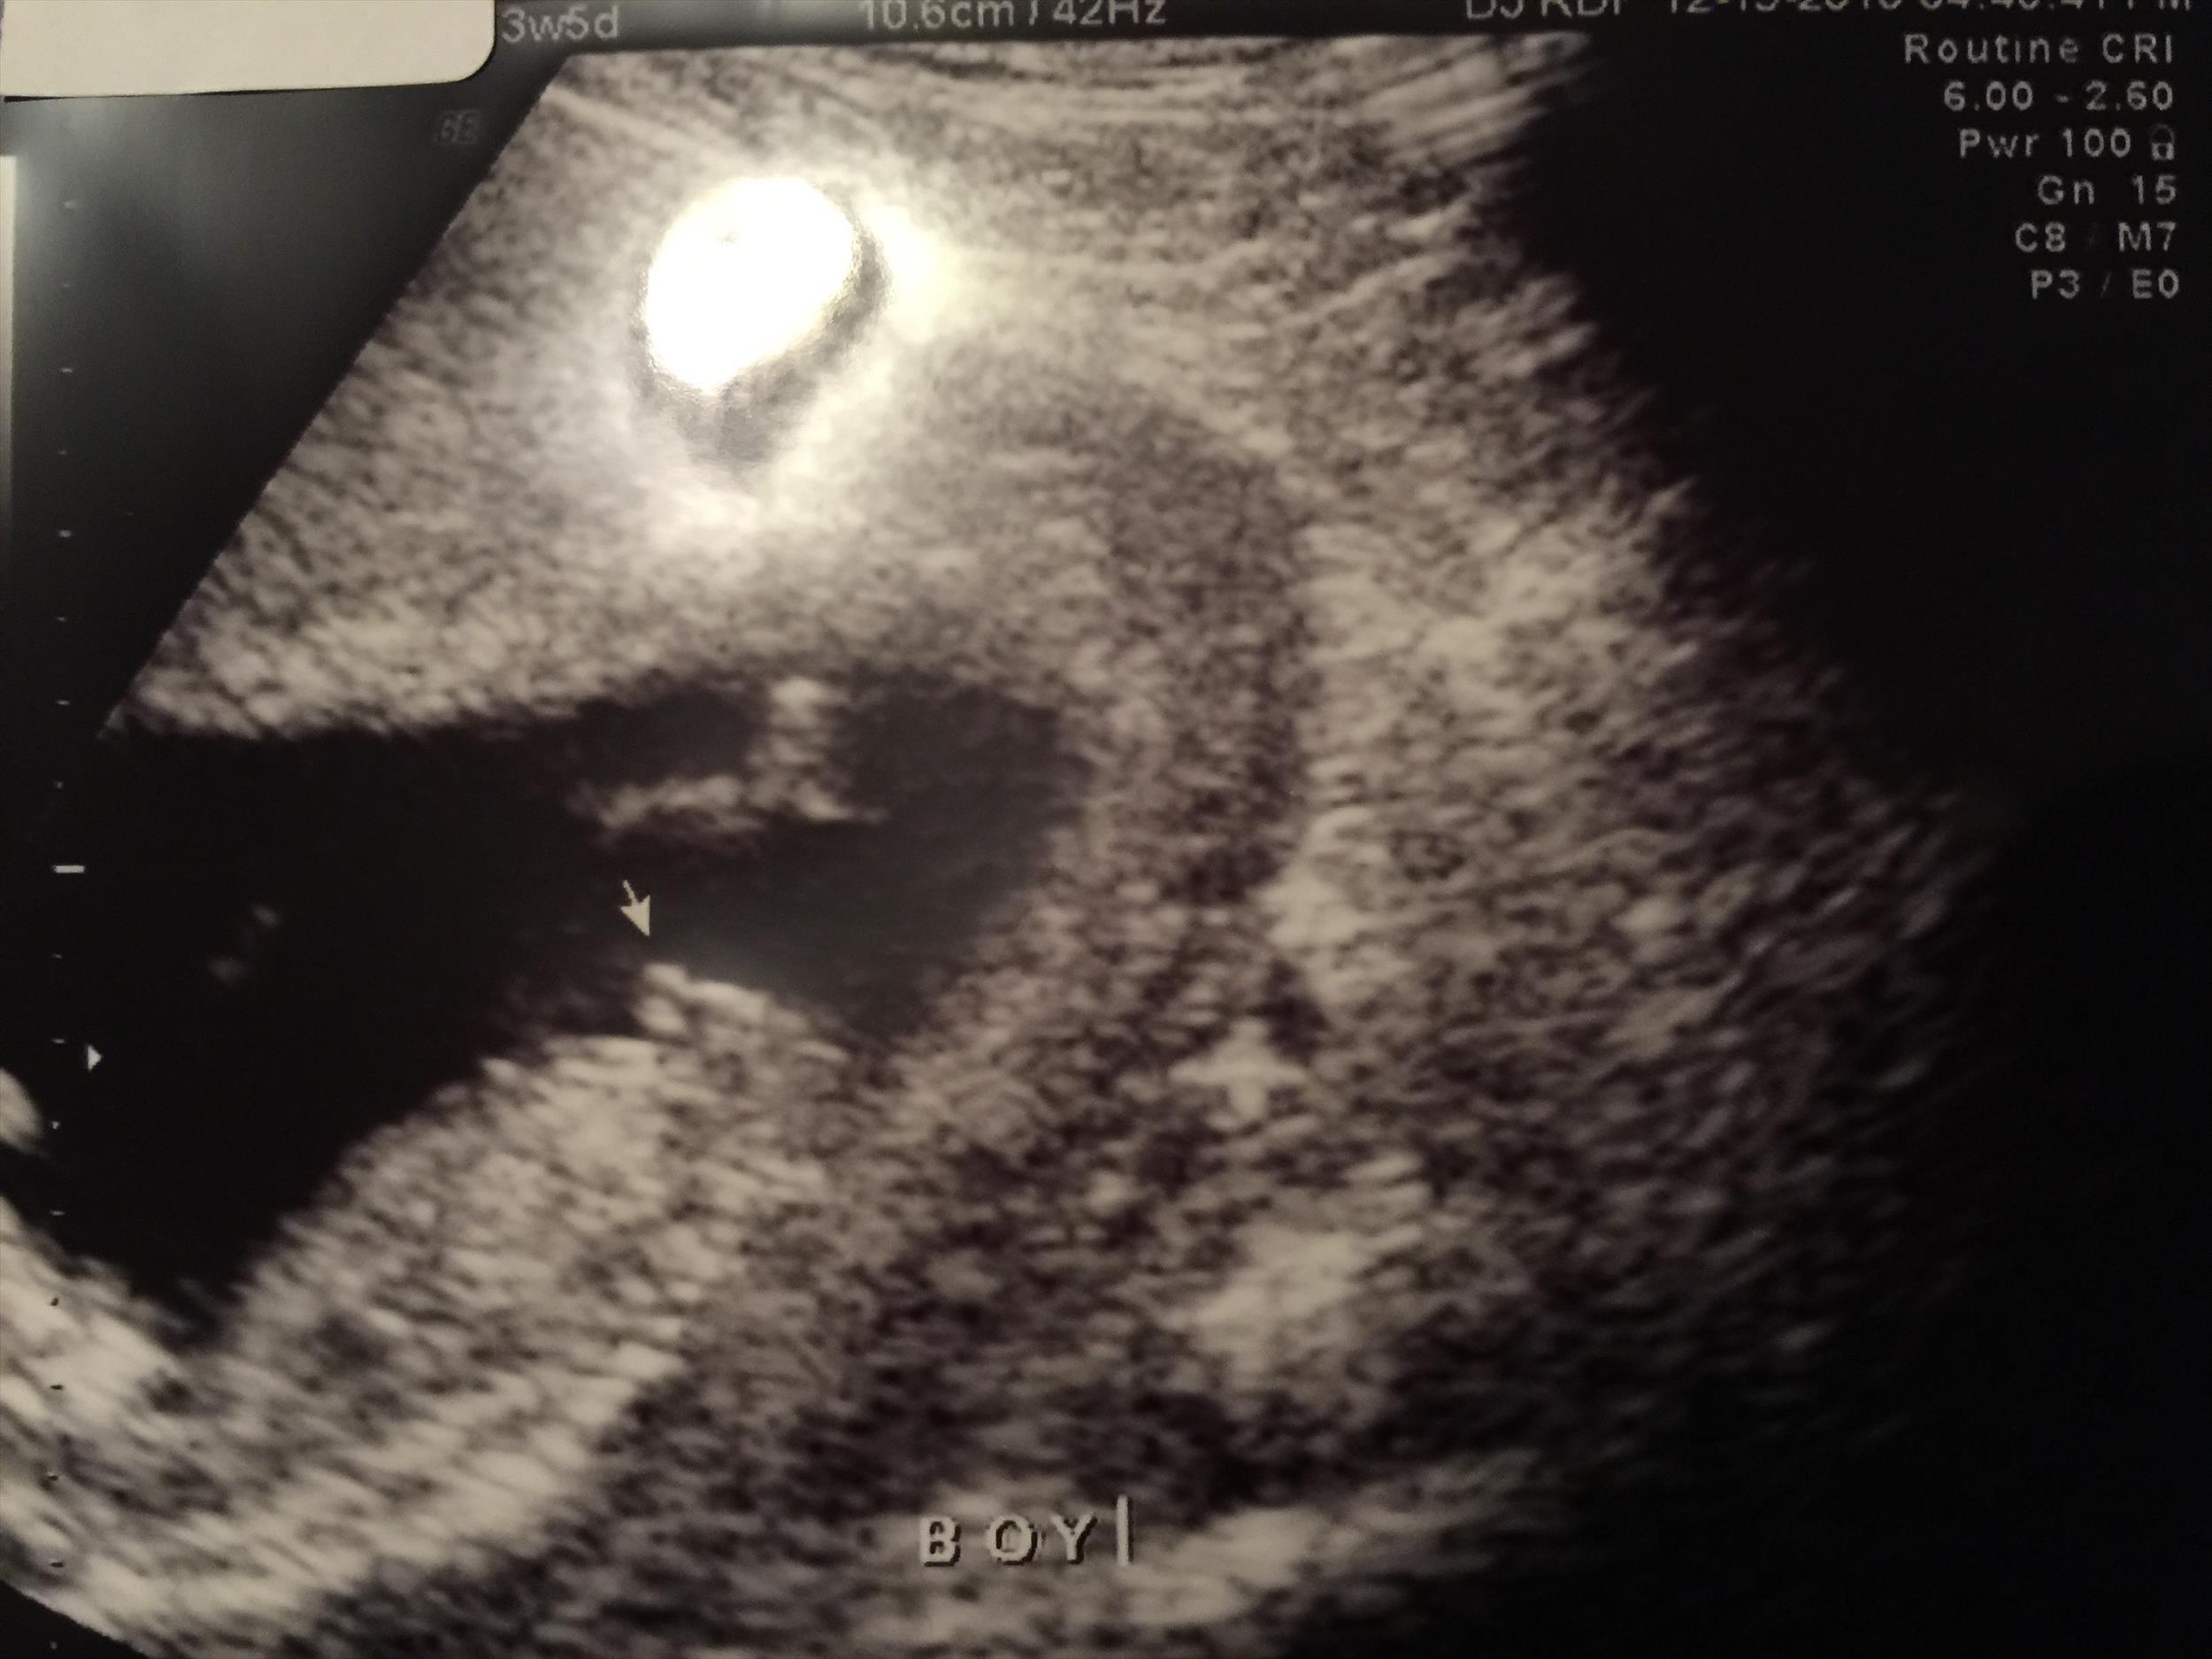

Just got a gender ultrasound at 13wk5d. Sonographer says "boy" but I wanted to make sure she didn't make a mistake. Please let me know if it's pretty obvious in these pictures. Thanks so much :)